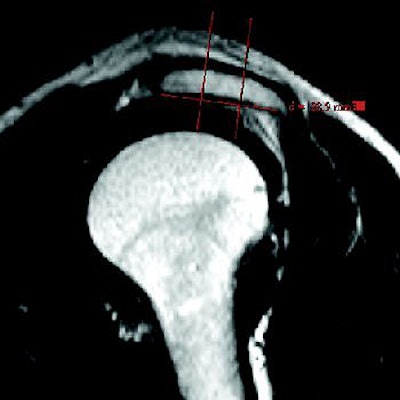

![]() |

| Mathematic determination of acromial shape. Line connecting most caudal points of acromial undersurface is drawn on parasagittal T2-weighted MR image, and with help of two orthogonal lines, acromion is divided into three segments of equal length. |